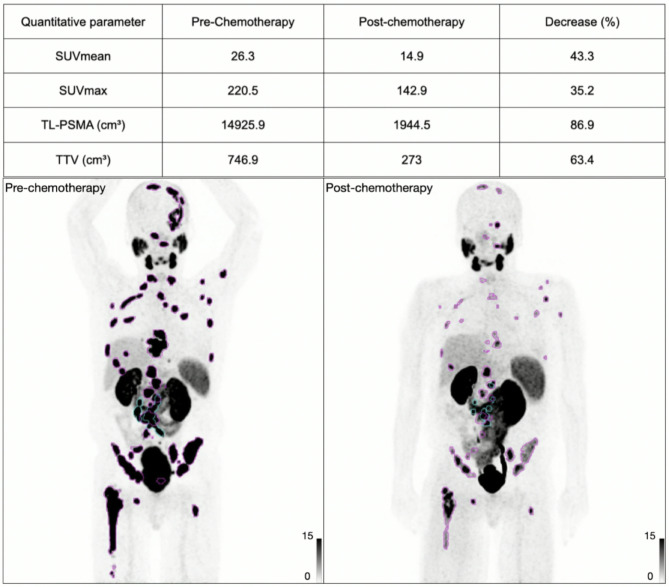

Pre- or post-chemotherapy: effect on PSMA uptake.